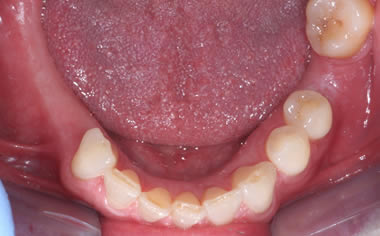

More back teeth replaced by dental implants

Case Five (4 images)